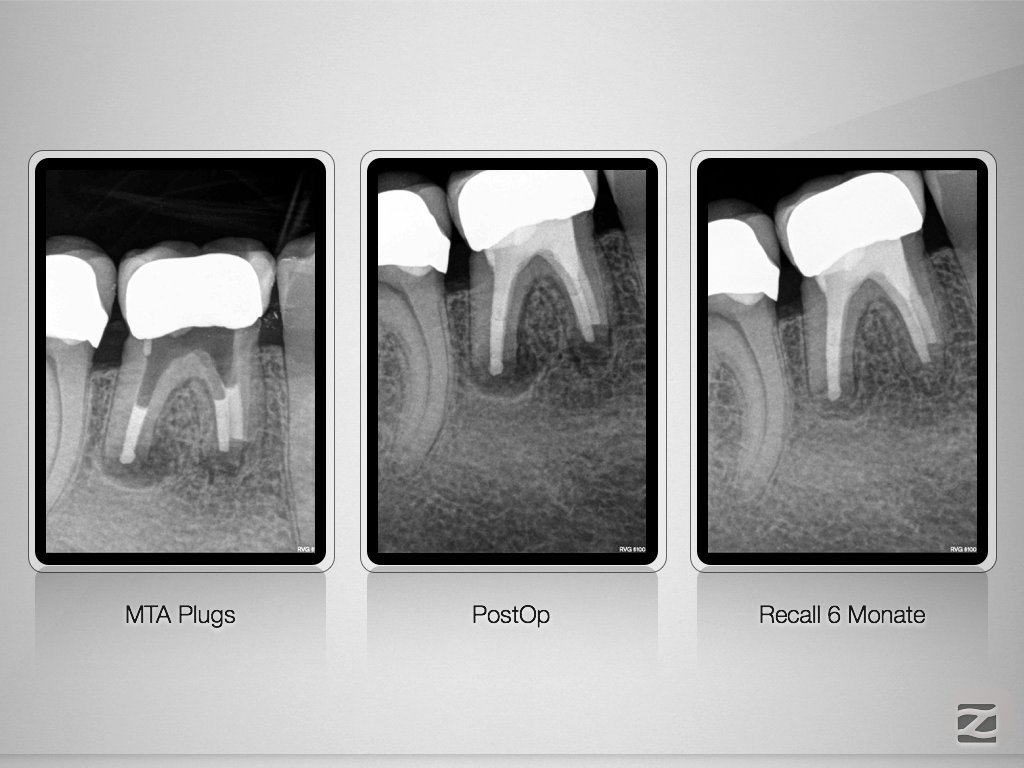

46d-009

Warten auf’s Recall